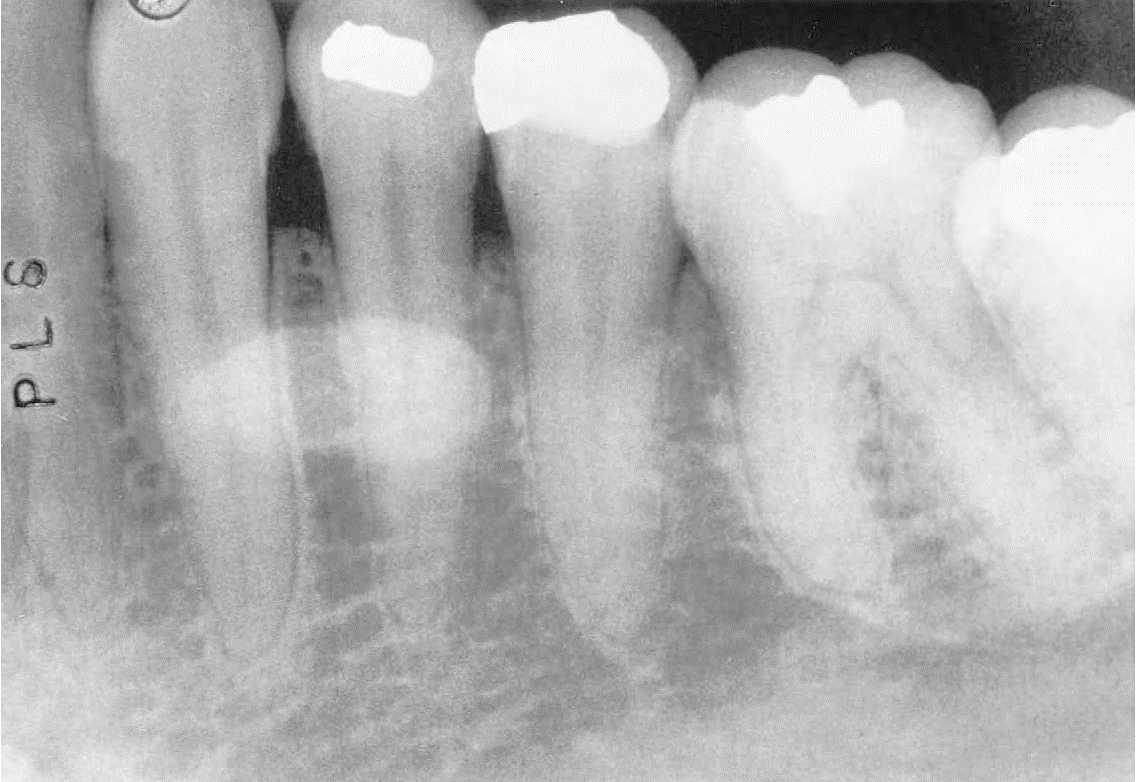

10. (Select ONE OR MORE correct answers)

The radiograph shows evidence of